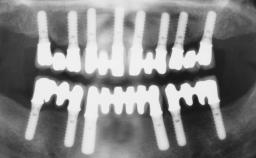

Immediate Loading of Six Implants in the Mandible and Six Implants in the Maxilla and Final Restoration with Full-Arch CAD/CAM Metal Framework FDPs Involving Digital Planning and Guided Surgery

Immediate loading of dental implants is increasingly popular with clinicians and patients. The idea of delivering a restoration directly after implant insertion,combined with a less invasive procedure (flapless protocol), has made treatment protocols involving dental implants more accessible to dentists and patients. However,immediate-loading concepts require sophisticated and exact planning. To facilitate this, conventional panoramic tomographs and periapical radiographs are often taken with the patient wearing a radiographic template simulating the preoperative prosthetic design. However, these radiographs do not provide all the necessary information. In addition, some protocols call for conventional surgical templates fabricated on the diagnostic cast. These will inform the bone drilling points and drill angles, but do not reference the underlying anatomical structures or provide exact 3-D guidance.

Guided Surgery Yes

Modality 6+ implants with immediate loading